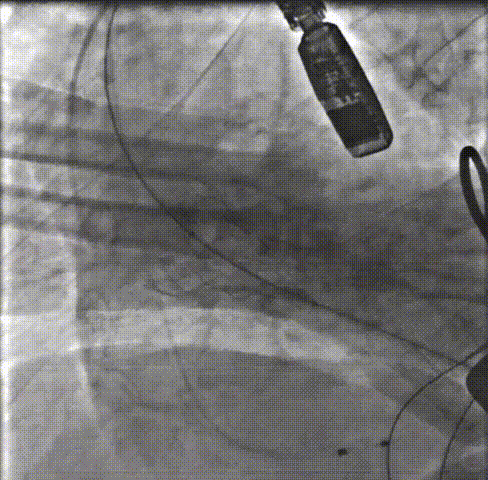

瓣膜释放前根部造影瓣膜打开到80%,再次行主动脉根部造影,支架高度和植入深度满意,不需要回收,直接释放瓣膜。

释放瓣膜:0位匀速释放Xcor-26瓣膜流入端。